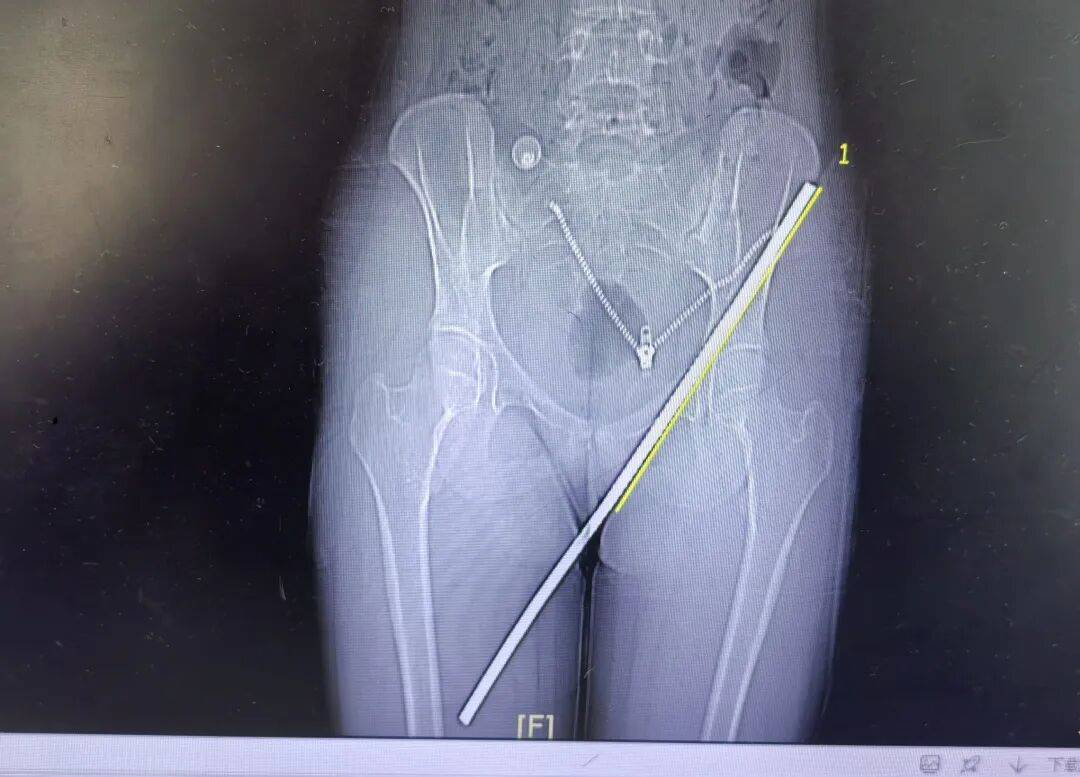

由于钢筋长达19厘米,且插入位置特殊,手术难度较大,医护人员凭借丰富的临床经验和精湛的医疗技术,成功将钢筋取出并完成伤口清创缝合、组织修复等步骤。目前,女孩生命体征平稳,已脱离生命危险,正在进一步康复治疗中。